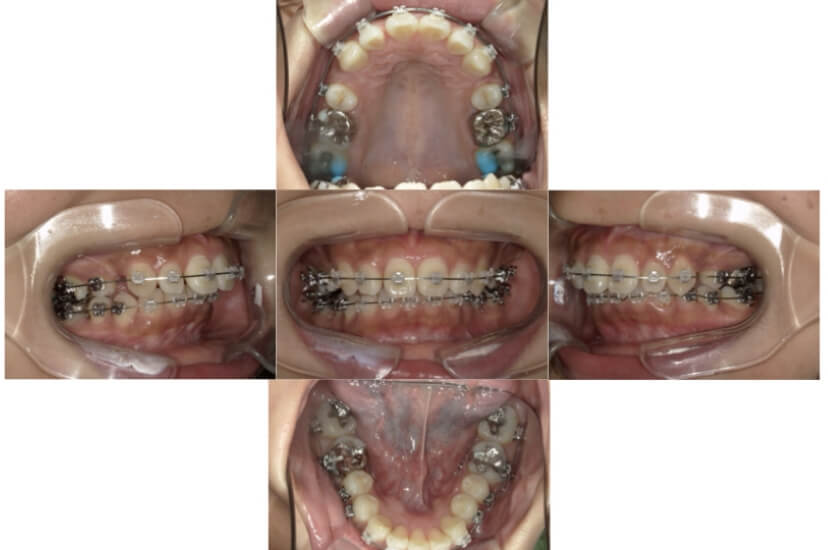

BEFORE

上下顎叢生(上下の前歯のガタガタ)のケースです。

装置はラビアル(上下表側)で、上下顎の小臼歯を4本抜歯を行っています。抜歯したスペースを利用し、上下の前歯の後方移動と叢生(ガタガタ)の改善を行っています。歯科用アンカースクリューを使用することで、可能な限り前歯を後方移動させています。

主訴 上下の前歯のガタガタで歯が磨きづらい。

年齢・性別 16歳 男性

お住まいの地域 東京都中央区

治療方針 抜歯スペースを利用して上下前歯の叢生(ガタガタ)の改善

抜歯部位 上下顎左右第一小臼歯

使用装置 ラビアル(上下表側)、顎間ゴム、歯科用アンカースクリュー

治療期間 2年3か月

治療回数 24回

リテーナー クリアリテーナー